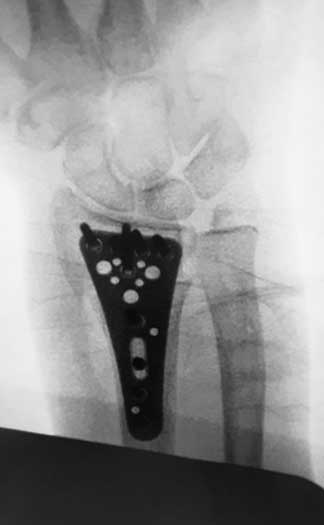

Imagen fluoroscópica de femenino de la tercera década de la vida, que tuvo fractura de muñeca practicando alpinismo. se observa una miniplaca anatómica.

Abordaje mínimo invasivo. en paciente femenina operada de reduccion de fractura de muñeca con placa anatómica.